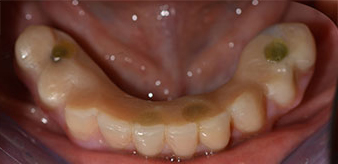

La paciente de 64 años se presentó con una dentición residual compuesta por las piezas dentales 38, 33 y 43 en el maxilar inferior y con una prótesis temporal fijada con ganchos en el maxilar inferior (figs. 1 y 2).